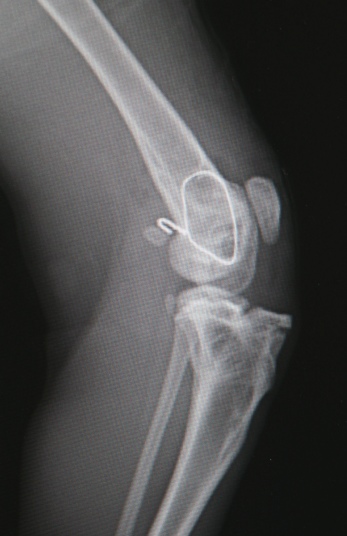

生後5ヶ月の時に車に撥ねられてしまいました。気胸と胸腔内出血もあり、事故から4日後になって容態が安定してからの手術になりました。膝関節のすぐ上の非常に固定しにくい部位でしたが、手術用電動ドリルの威力で、短時間で非常にうまく固定することが出来ました。幸い温和しい性格の子でしたので、オーナー様の管理も比較的順調に出来、術後2ヶ月で避妊手術の時にピンも抜けました。